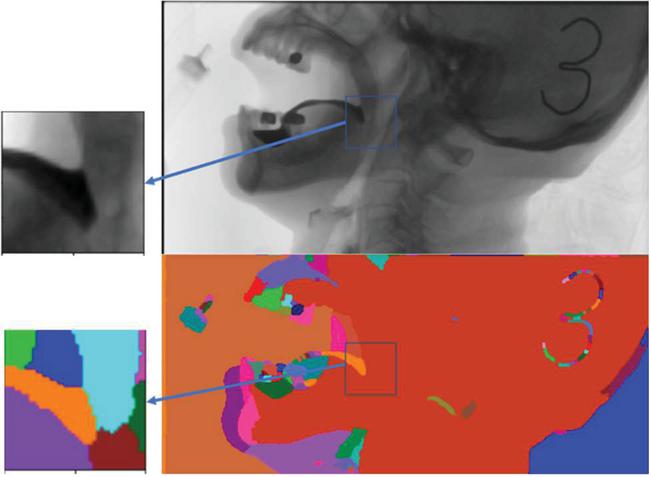

images

Figure 2 This case demonstrates a simplified procedure for the extraction of a patient’s piriform fossa.

The premise of our work is to judge a single frame from the original barium recognition, and gradually transfer to the determination of tissues and organs through the barium recognition. Why accurate tracking, only the complete track of barium agent, to facilitate the later determination of barium agent in each organ stay position, time and quantitative study. We used morphological methods to extract barium. Due to the quality difference of the original film, the expected errors of the barium trace area deviation in this experiment were within -25%25%.